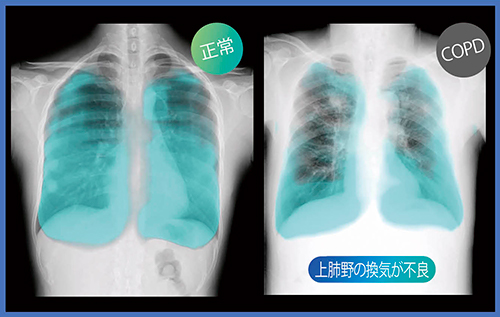

図3は,慢性閉塞性肺疾患(COPD)である。KINOSISで呼吸に伴う肺野内の濃度変化を見ると,正常例と比べ,上肺野の換気が不良であることがわかる。従来は肺機能検査(スパイロメーター)を施行しなければ診断できなかったが,X線動態撮影により動画像で換気を観察することが可能になった。

図3 COPDの肺野内濃度変化